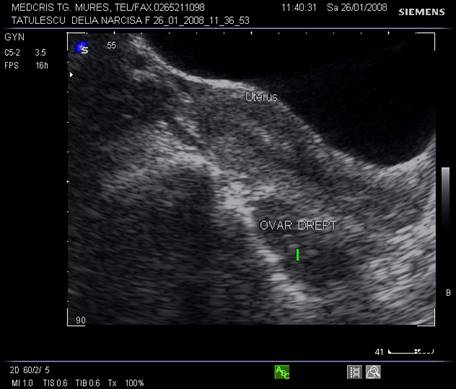

Ovarele. Sectiunea longitudinala directa, spre peretele lateral pelvin, la ecografia transvaginala, pune in evidenta ovarele cu forma elipsoidala. Acestea au structura ecografica relativ slab ecogena, in apropierea si sub vasele iliace.[5]

Marimea ovarelor: inainte de menopauza aproximativ 3,5 x 2,5 x 1,5 cm si aproximativ 2,0 x 1,5 x 1 cm dupa menopauza. Nu se poate aprecia volumul ovarian decat masurand cele trei diametre in planuri sagitale, oblice si coronale ale pelvisului.[1,2,9]